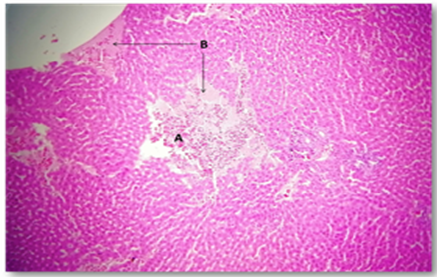

3.6 Microscopic analysis of liver tissue

The liver tissue's microscopic examination exposed evidence of hemorrhage and hemolysis, alongside significant inflammatory cell infiltration around the portal vein. A notable presence of macrophages (Kupffer cells) within the sinusoids was also observed. Moreover [33], fatty necrosis was prevalent in a majority of hepatocytes, highlighting the protective and reparative roles of chitosan against liver damage induced by stress factors and possibly by the metabolic disturbances associated with fungal infections, as shown in Figures 4-9, which starkly contrast the findings in the control group.

Figure 5. The histological slice of the chitosan-treated liver revealed: A) Inflammatory lymphatic infiltrate within portal area, B) Sinusoid were filled with kuppfer cells